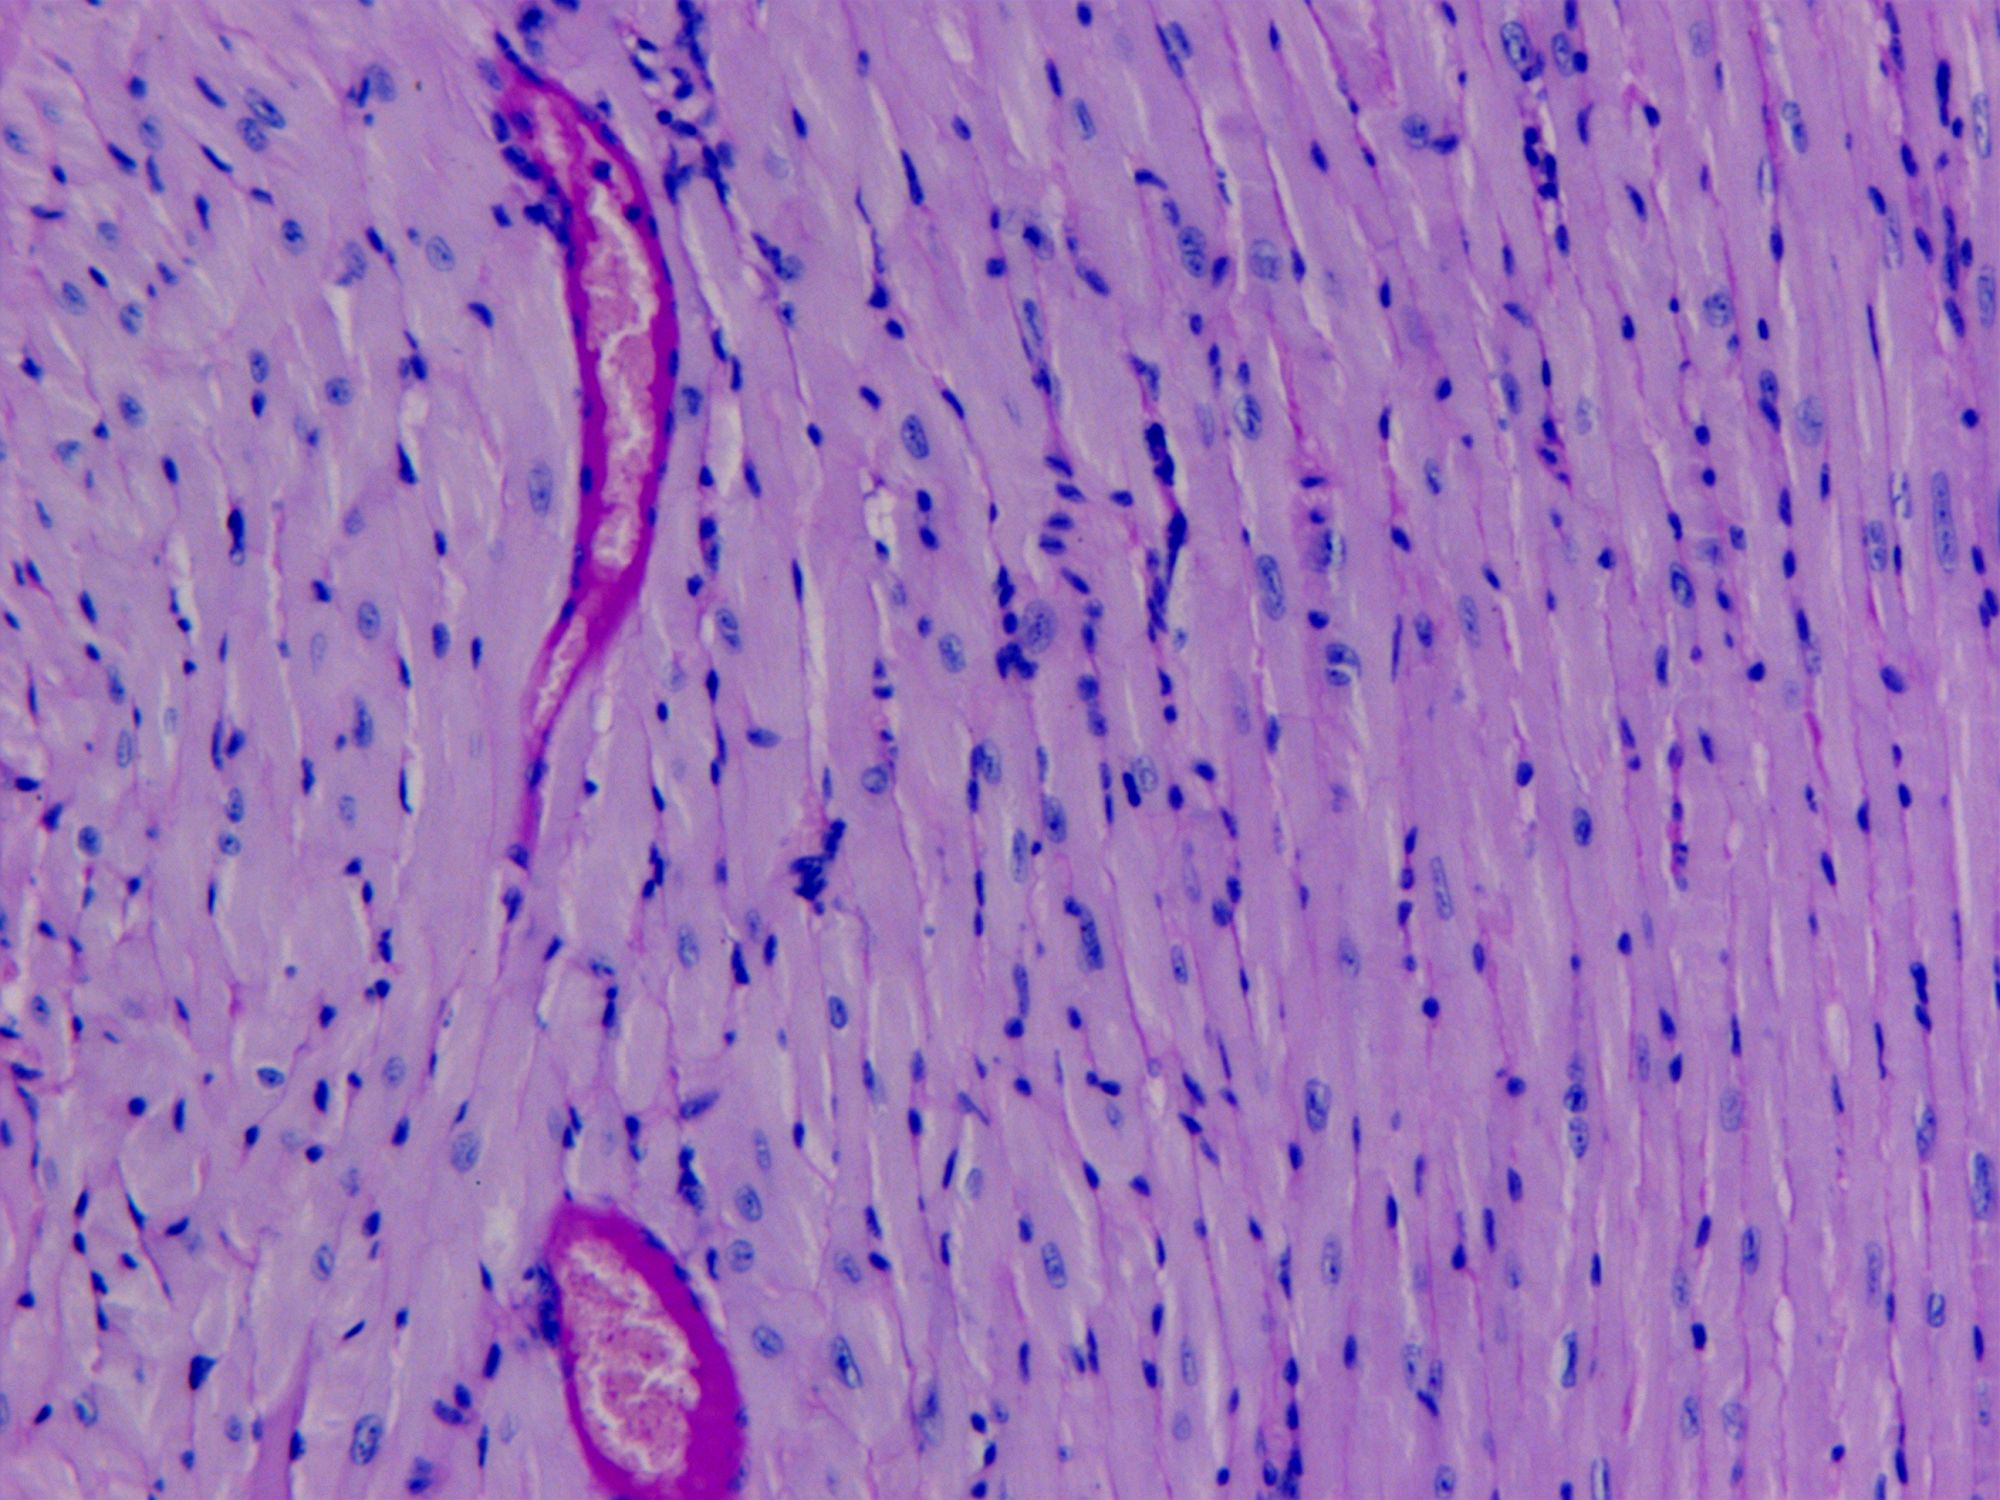

PAS染色法(Periodic Acid-Schiff stain)在組織學(xué)上,又稱過(guò)碘酸雪夫染色,糖原染色。一般用來(lái)顯示糖元和其它多糖物質(zhì),過(guò)碘酸把糖類相鄰兩個(gè)碳上的羥基氧化成醛基,再用Schiff試劑和醛基反應(yīng)使呈現(xiàn)紫紅色。

PAS染色糖原染色是病理學(xué)中常規(guī)的染色方法之一,氧化劑能氧化糖類及有關(guān)物質(zhì)中的1,2-乙二醇基,使之變?yōu)槎?,醛與Schiff試劑能結(jié)合成一種品紅化合物,產(chǎn)生紫紅色。PAS技術(shù)常用來(lái)顯示糖原和其他多糖,該染色液不僅能夠顯示糖原,還能顯示中性黏液性物質(zhì)和某些酸性物質(zhì),以及軟骨、垂體、霉菌、真菌、色素、淀粉樣物質(zhì)、基底膜等。

PAS反應(yīng)陽(yáng)性物質(zhì) 紅色或紫紅色

細(xì)胞核 藍(lán)色

細(xì)胞質(zhì) 深淺不一的紅色